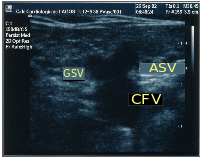

Particular veins of the DVS and the SVS are looked at. The great saphenous vein (GSV) is a superficial vein which connects with the small saphenous vein (SSV) to drain into the common femoral vein (CFV). Perforator veins drain superficial veins into the deep veins. Three anatomic compartments are described (as networks), (N1) containing the deep veins, (N2) containing the perforator veins, and (N3) containing the superficial veins, known as the saphenous compartment,. This compartmentalisation makes it easier for the examiner to systematize and map. The GSV can be located in the saphenous compartment where together with the Giacomini vein and the accessory saphenous vein (ASV) an image resembling an eye, known as the 'eye sign' can be seen. The ASV which is often responsible for varicose veins, can be located at the 'alignment sign', where it is seen to align with the femoral vessels. Together with the GSV and the CFV these three veins create an image called the 'Mickey Mouse' sign. The examination report will include details of the deep and the superficial vein systems, and their mapping. The mapping is drawn on paper and then drawn on the patient before surgery.

Accessory saphenous vein